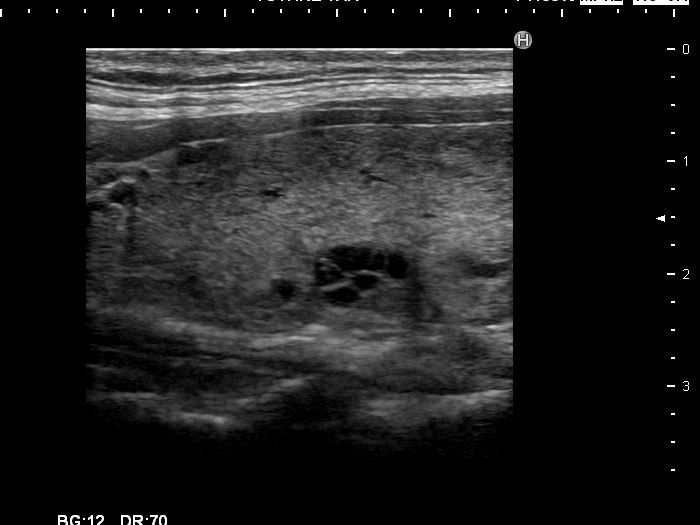

Graves' disease - case 799

Follow-up examination 12 months after the first visit (ultrasonographic picture 5)

Upper part of the left lobe, longitudinal scan. This lobe also has cystic lesions.